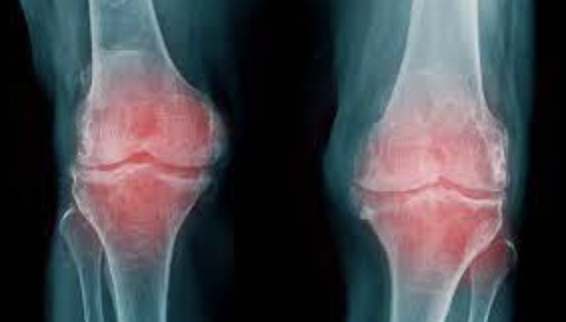

Glutation y Artrosis

By administrator | July 4, 2023 | Comments Off on Glutation y Artrosis

El glutatión es un antioxidante crucial que desempeña un papel importante en la protección del organismo contra el estrés oxidativo y la inflamación. Se ha demostrado que sus propiedades antioxidantes y antiinflamatorias pueden ser beneficiosas en el contexto de enfermedades articulares como la artrosis. A continuación, se presentan algunos posibles beneficios del glutatión en relación…